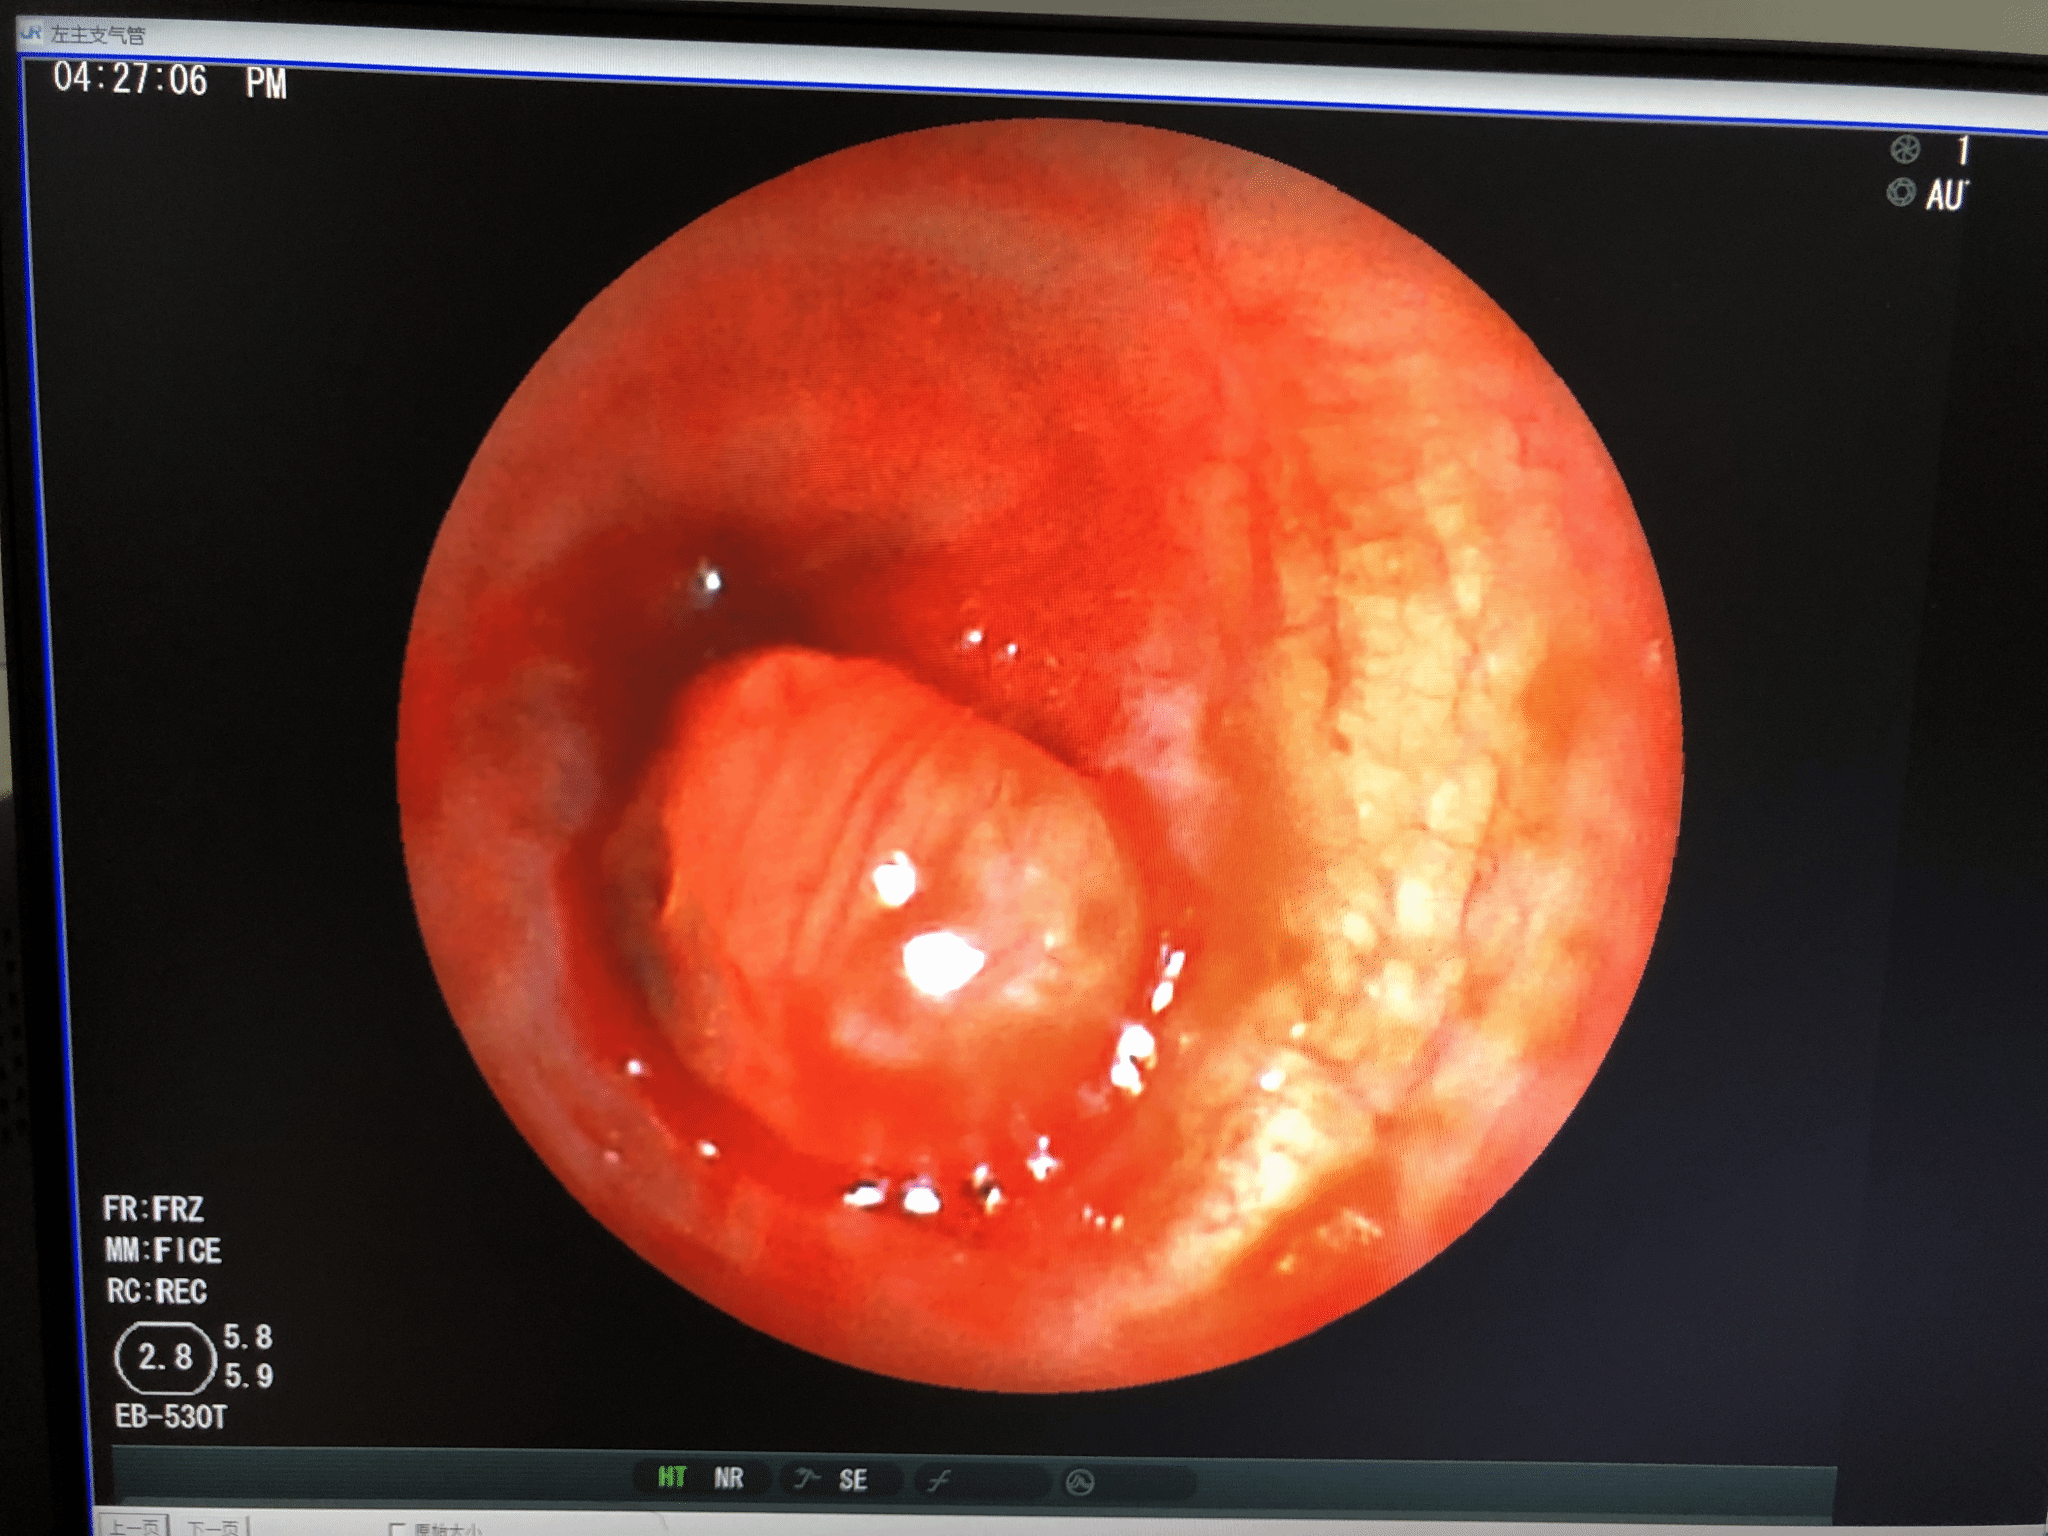

无痛支气管镜检查术